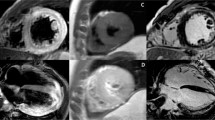

Late gadolinium enhancement (LGE) was originally thought to demonstrate irreversible myocardial injury only, however several studies have demonstrated a temporal change in the extent of LGE in myocarditis, with LGE volume seen to decrease significantly over time (follow up scans performed between 1 and 18 months) [3, 36–38, 40, 45]. Histological correlation has shown LGE is associated with active inflammation, with the extent of LGE corresponding to the severity of the inflammatory histopathological findings [45, 46]. It is likely that LGE in acute myocarditis represents both reversible and irreversible myocardial injury, but in the chronic phase represents residual focal fibrosis. See Fig. 1a for a representative example.

Patient with acute viral myocarditis. a Late enhancement imaging. Epicardial and mid-wall late enhancement (green arrows) in mid anterolateral and apical lateral segments. b T1 mapping, MOLLI sequence. Elevated T1 values in mid-wall and epicardial portion of basal—mid anterolateral and apical lateral segments (green arrows; T1 values in anterolateral wall: 1152 ms, T1 values in basal inferoseptum: 1031 ms). c T2 mapping, T2-prepared SFFP sequence. Elevated T2 values in epicardial portion of mid anterolateral and apical lateral segments (green arrows; T2 values in mid anterolateral segment: 66 ms, T2 values in basal inferoseptum: 47 ms)

In recent years, parametric mapping, which allows direct quantification of myocardial tissue magnetic parameters (primarily T1 and T2) has been increasingly applied in myocarditis. (Similar to T2, T1 relaxation times are sensitive to changes in myocardial water content and have been proposed to detect myocardial oedema). As well as being associated with potentially less observer variability, less artefact and allowing global myocardial assessment, native T1 and T2 mapping offer the significant advantage of not requiring contrast agent administration. See Fig. 1b, c for representative examples.